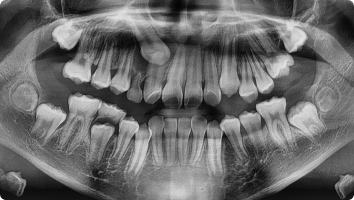

앞니 한가운데 잇몸 뼈 속에 필요 없는 치아가 숨어 있는 경우를 말합니다.

이 치아는 앞니 배열을 방해하거나 영구치가 나오지 못하게 할 수 있어,

보통 조기에 발견하면 발치해 주는 것이 좋습니다.

- 국소마취 하에 잇몸을 살짝 열고 숨어 있는 과잉치만 조심스럽게 제거합니다.

- 이후 잇몸을 봉합해 안전하게 회복되도록 합니다.

수술은 짧은 시간에 안전하게 진행되며, 대부분 아이들은 수술 후 큰 불편 없이 회복합니다.